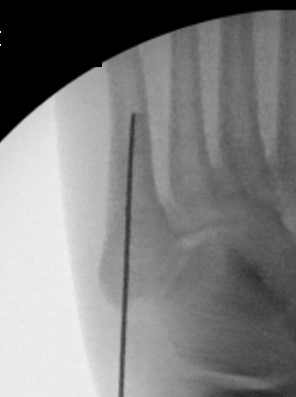

Technique

Entry point

- 5th metatarsal is not straight

- high and medial to get straight shot

- avoids plantar insertion peroneus brevis

- screw diameter 3.5 / 4.5 / 5.5 / 6.5

- screw threads must be distal to fracture site to allow compression